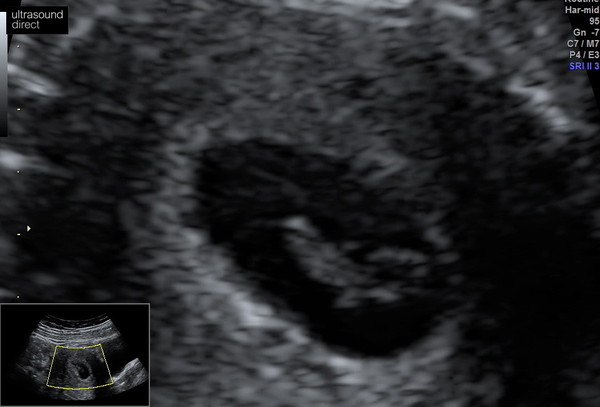

Hi all, the scan went great! All good and the heart is beating. I was surprised they didn’t do a transvaginal as the pictures would have been much clearer. They didn’t do a dipper ether to see the exact heartbeat rate. They say they can see it’s all looking very good and the exact number at this early stage would only make parents nervous as the normal range is to wide.

I tested up a bit when I saw this little heart beating ❤️❤️❤️ Hope you all have a wonderful weekend despite the rain!

"Teared up"

Wow beautiful pic @Viletta 🤗🥰👍🏻 I bet you are bit relaxed now xx

Aw congratulations @Viletta ❤️❤️❤️ I felt quite emotional seeing your scan picture so god knows what I will be like with my own! 🙈

Thank you everyone:)) it was amazing seeing the heartbeat movement. Definitely feeling more relaxed now and I think I'll just try to enjoy the whole thing till the next 12 week scan.

Absolutely beautiful picture @Viletta!! 😍 I've also got a tear in my eye looking at it - a happy tear, of course! 😊 I can only hope that we get the same kind of good news as yours on Tuesday 🔮🤞